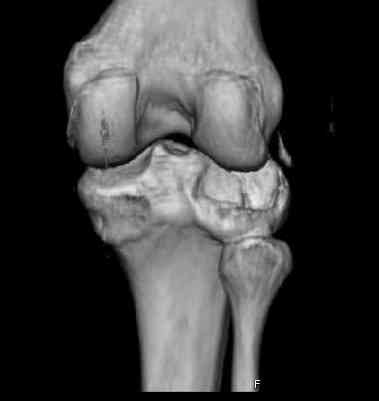

Здравствуйте, уважаемые коллеги!Подскажите, пожалуйста, какой выбрать доступ и способ фиксации при импрессионном переломе заднего отдела наружного мыщелка большеберцовой кости. Женщина 40 лет, травму получила 02.01.2008, катаясь на горных лыжах.Есть ли здесь необходимость использовать задний доступ, или можно справиться через наружный? Есть ли шансы сделать закрыто - под ЭОП через медиальное "окошко" поднять забойником суставную поврехность? Какой лучше использовать фиксатор?Спасибо.

центральная импрессия, а при ипрессии с краевым переломом - после приподнимания импрессии опорная (Butress) пластина, как на снимке.